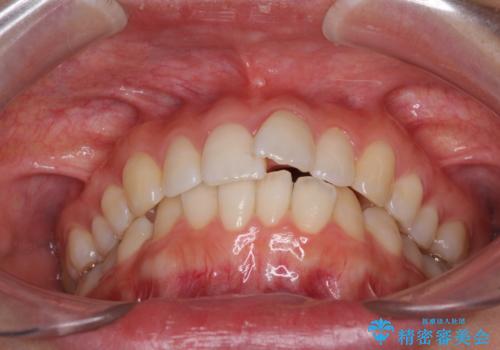

口が閉じにくい 1本飛び出した前歯の矯正治療

- 1本飛び出した前歯を治したいとのことで来院された患者様です。

歯列全体の拡大とIPR(歯と歯の間を削る)によってデコボコが解消するようにし、さらにゴムかけを活用して右側の咬み合わせ位置を変えるように設計し、インビザラインにより治療を行うこととしました。

結婚式までに前歯を整えたいとのことでしたが、インビザラインでは先に奥歯を移動させてから前歯を動かすため、間に合わない可能性がありました。しかし、結婚式までに期間があったことと、マウスピースをしっかりと装着してくださったことで、十分な歯列に整えることができました。